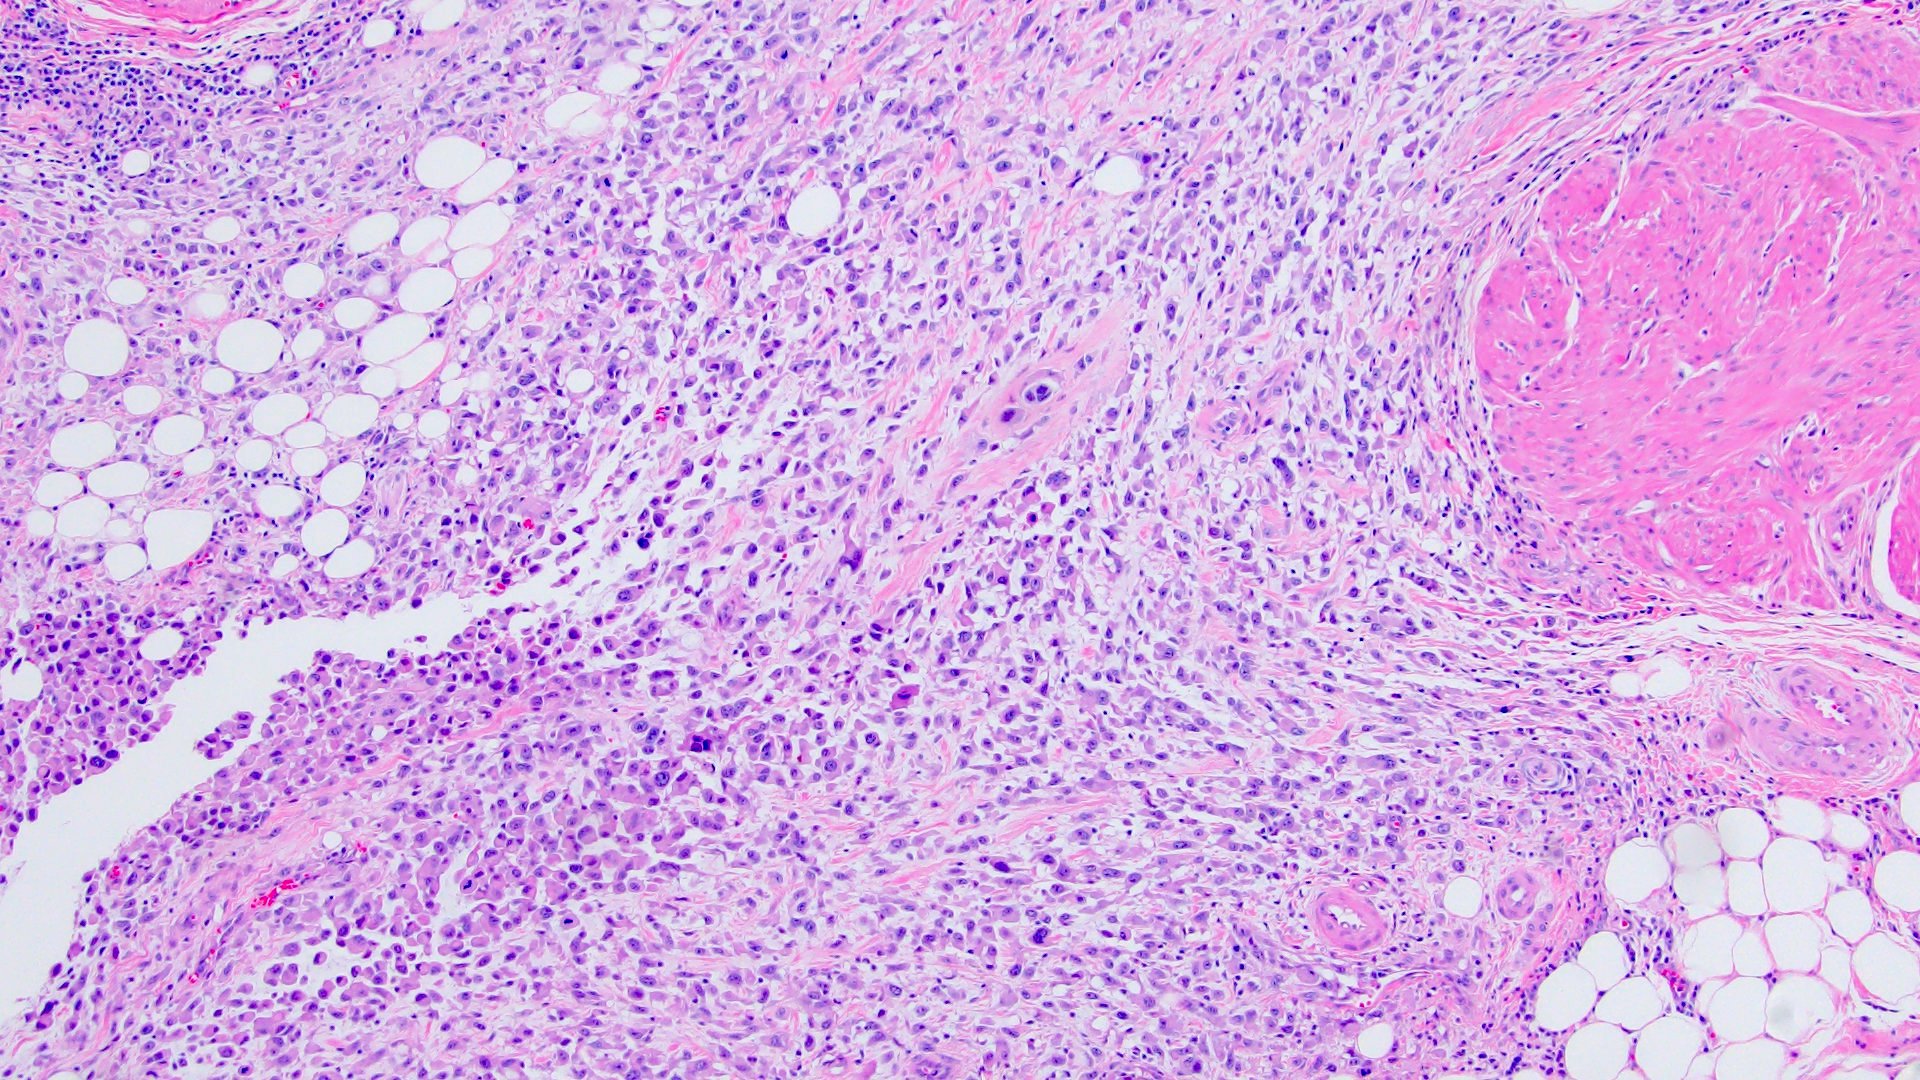

Microscopic (histologic) description

- Discohesive single cells with eccentrically placed nuclei and abundant eosinophilic cytoplasm

- Often deeply infiltrative but with minimal stromal reaction (Eur Urol Focus 2020;6:653)

- Further subclassified into classic, pleomorphic and desmoplastic subtypes:

- Classic: signet ring-like morphology, singly scattered and discohesive in loose aggregates forming cords (Hum Pathol 2019;90:27)

- Pleomorphic: similar to classic but with pleomorphic nuclei and more atypia; can be rhabdoid and bizarre appearing (Hum Pathol 2019;90:27)

- Desmoplastic: plasmacytoid neoplastic cells with a surrounding desmoplastic stromal response (Hum Pathol 2019;90:27)

- Associated with sarcomatoid variant in 31% of cases (Hum Pathol 2019;90:27)

- Often mixed with other histologic subtypes; in 1 case series, 53% of PUC had mixed histologic subtypes (Am J Clin Pathol 2017;147:500)

- Despite resemblance to signet ring carcinoma cells, notably lack extracellular mucin, contrasting to signet ring adenocarcinoma (Acta Cytol 1991;35:277, Am J Surg Pathol 1991;15:569)

Microscopic (histologic) images

Contributed by Timothy Isaac Miller, M.D., M.A., Nicole K. Andeen, M.D. and Maria Tretiakova, M.D., Ph.D.

Contributed by Lisa Han, M.D. and Ricardo Lastra, M.D. (Case #510)